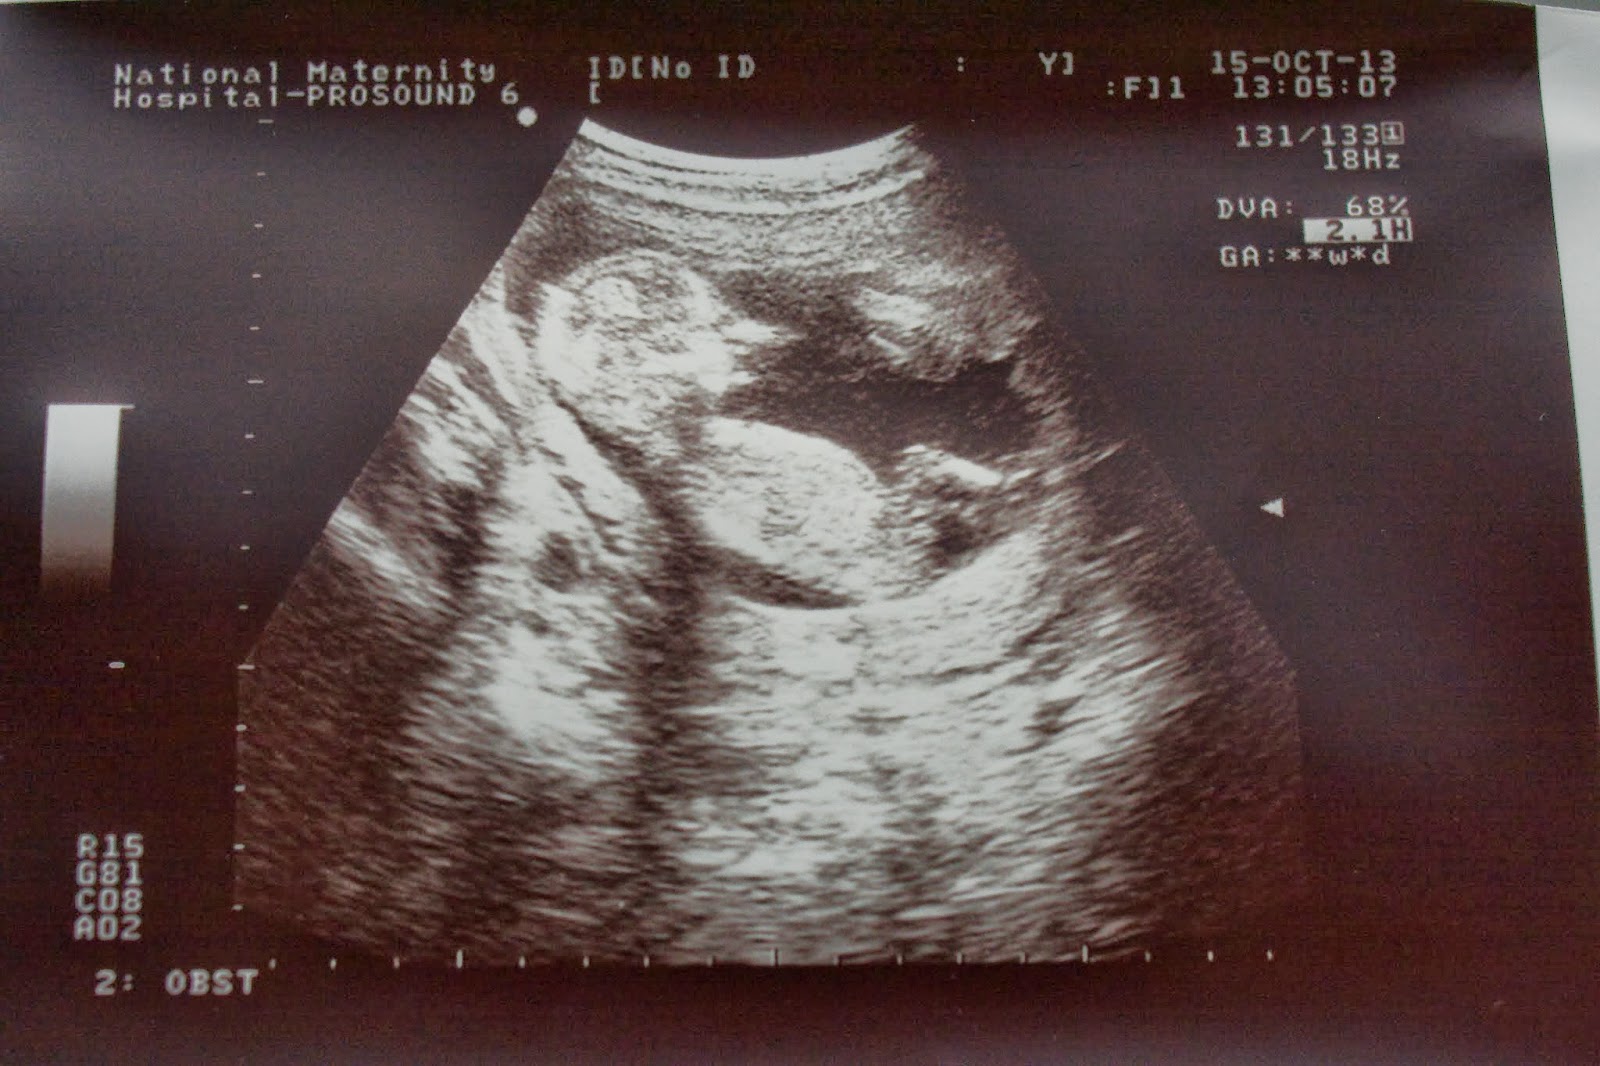

Ezek után csinált egy hasi ultrahangot. Kicsit magyarázott az orvostanulónak. Mindent rendben találtak. Megkérdezte, hogy kérek-e egy fényképet. Természetesen kértem ;)